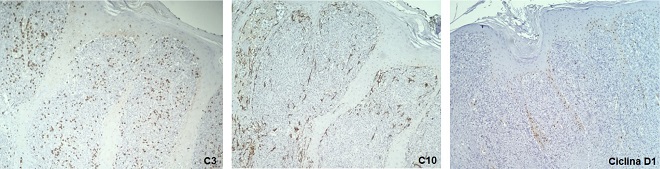

A Caucasian, 81-year-old woman came to the Dermatology Outpatient Clinic complaining of fast-growing “lumps” on her left leg, with one-month evolution. Dermatological examination revealed vegetating nodules and tumors, with an erythematous-yellow fibrinoid surface and the presence of blackened crusts (Figure 1).There was no lymph node enlargement or visceromegaly. The lesions were painful, and the patient denied any systemic symptoms. She mentioned previous trauma as a triggering factor. Also, she had peripheral venous insufficiency and type II diabetes mellitus as comorbidities. The hypotheses put forward were squamous cell carcinoma, amelanotic melanoma, cutaneous metastases, and cutaneous lymphoma. Incisional biopsies were performed in two points. The histopathological study showed ulcerated epidermis with areas of necrosis and the presence of dense and diffuse lymphocytic infiltrate consisting of large cells in the superficial and deep dermis, sometimes with nuclei with irregular contours and abundant mitotic figures (Figure 2). The immunohistochemical panel was positive for Bcl-2, CD20, and MUM1 (Figure 3) and negative for CD3, CD10, and cyclin D1 (Figure 4), concluding a B-cell non-Hodgkin lymphoma diagnosis. Bcl-6 was not performed. The proliferative index by Ki-67 was 90%, and C-MYC was positive in about 30% of the cells (Figure 5).

The positivity of the markers Bcl-2, Bcl-6, MUM1, and FOXP1 is characteristic of this type of lymphoma.1,5 The positivity of C-MYC seems to be related to a worse prognosis.7,8 Other indicators of poor prognosis include lower limb location, multiple injuries, and age over 75 years.6